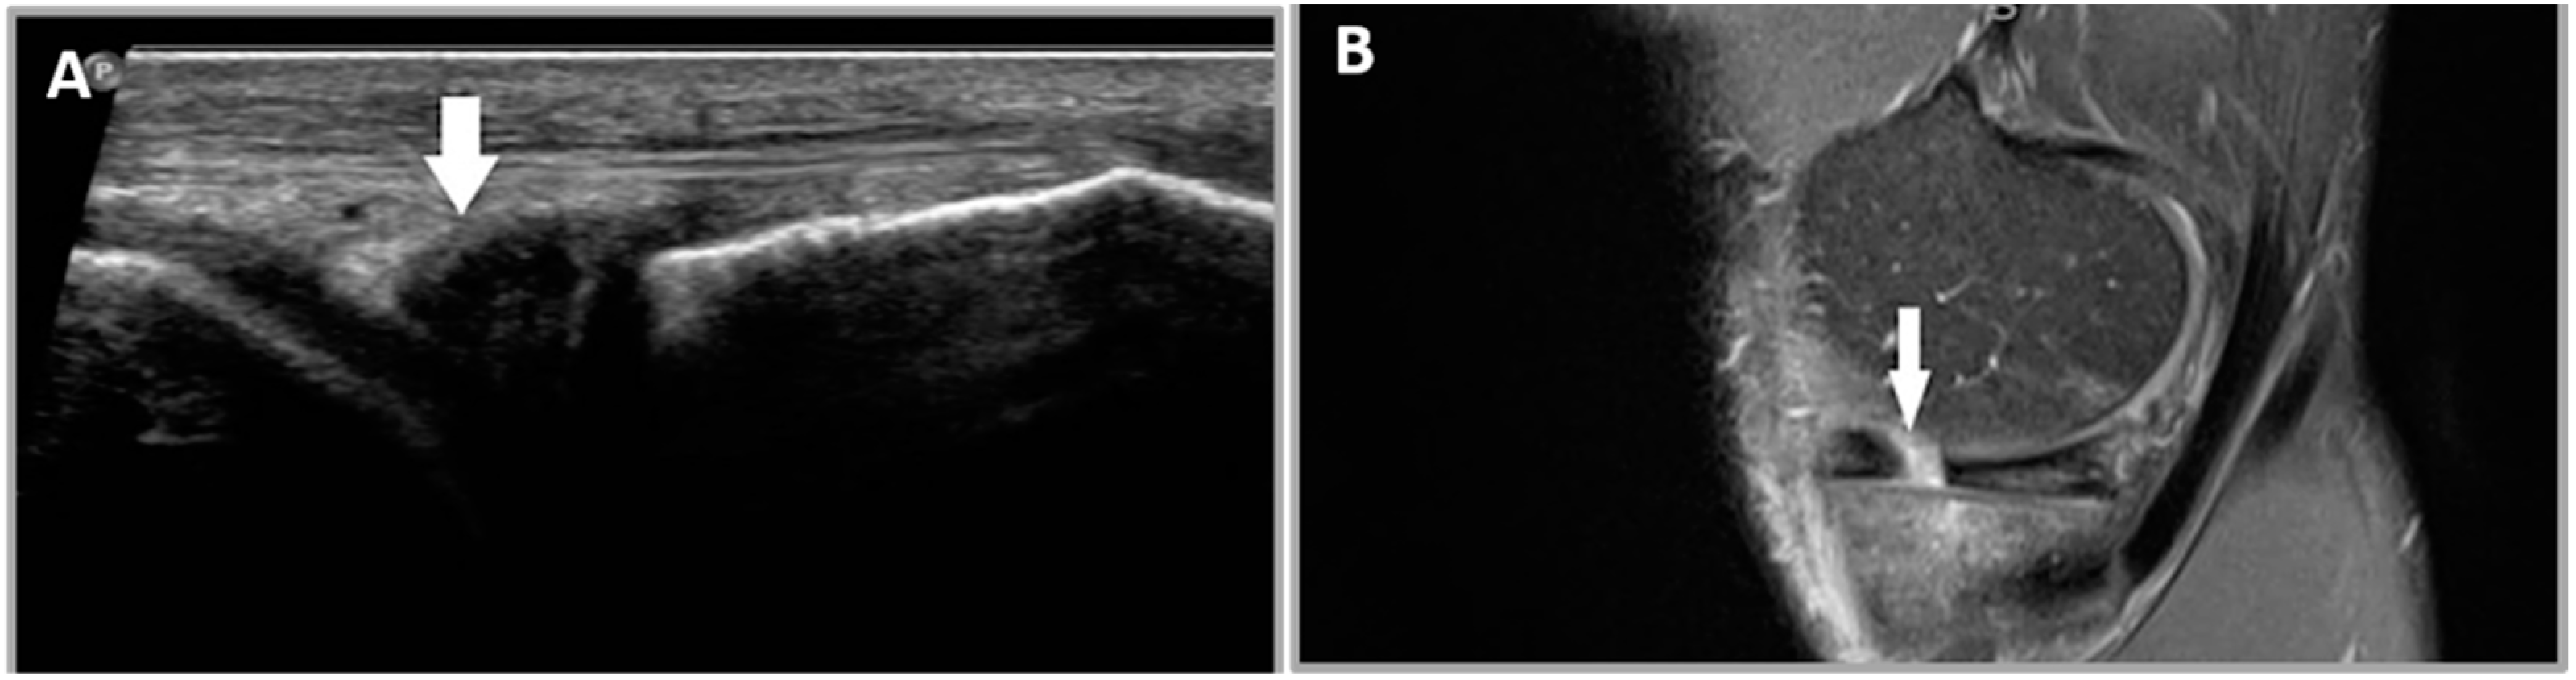

2.5.1. Criterion 1—Meniscal Cleft